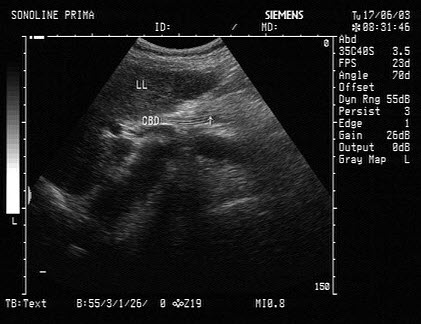

43、单项选择题 异位妊娠时,人类绒毛膜促性腺激素(HCG)滴度一般是()

如图,可见腹主动脉及其分支纵切超声图,图中与腹主动脉平行的分支为_______。